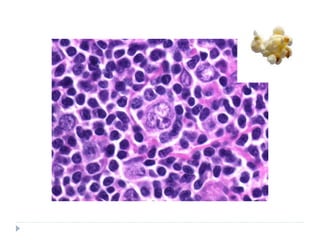

HISTOPATHOLOGY

 Common features

 Effacement of normal nodal architecture by diffuse mixed

infiltrate of inflammatory cells

 Interspersed with large ATYPICAL NEOPLASTIC

LYMPHOID CELLS

 In classic type this atypical cell is known as REED

STERNBERG CELL

 Malignant cell in nodular-lymphocyte predominant HL is

POPCORN CELL

 Reed sternberg cell

 Typically binucleated (owl-eye nuclei)

 Sometimes may also be multinucleated (pennies on a

plate) with prominent nucleoli

 Popcorn cell: nucleus resembles kernel of popped

corn